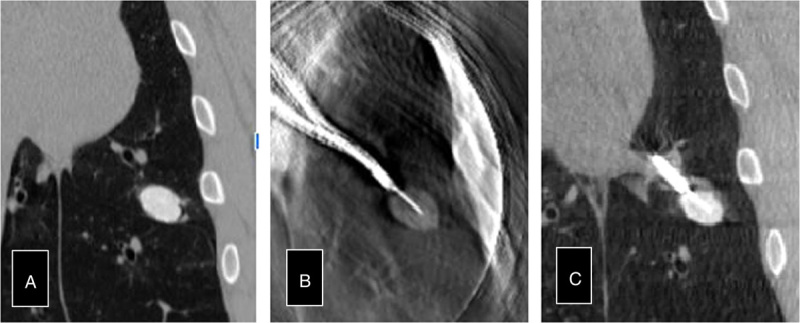

Methods: Four operators conducted the experiment using 4 pigs. Each physician performed between 4 and 6 nodule biopsies for 20 simulated lung nodules with purple dye and a radio pacifier. Using Galaxy's "Tool-in-Lesion Tomography (TOMO+)" with augmented fluoroscopy, the physician navigated to the lung nodules, and a tool (needle) was placed into the lesion. TIL was defined by the needle in the lesion determined by cone-beam CT.

Results: The lung nodule's average size was 16.3 ± 0.97 mm and was predominantly in the lower lobes (65%). All 4 operators successfully navigated to all (100%) of the lesions in an average of 3 minutes and 39 seconds. The median number of tomosynthesis sweeps was 3 and augmented fluoroscopy was utilized in most cases (17/20 or 85%). TIL after the final TOMO sweep was 95% (19/20) and tool-touch-lesion was 5% (1/20). Biopsy yielding purple pigmentation was also 100% (20/20).

Conclusion: The Galaxy System demonstrated successful digital TOMO confirmed TIL success in 95% (19/20) of lesions and tool-touch-lesion in 5% (1/20) as confirmed by cone-beam CT. Successful diagnostic yield was achieved in 100% (20/20) of lesions as confirmed by intralesional pigment acquisition.